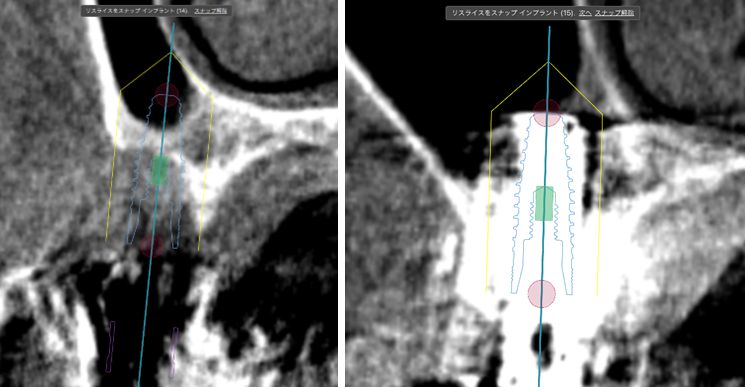

③ガイデッドサージェリーにてインプラント埋入しました。

④計画通りの埋入が出来ました。

術前ではインプラントを埋入する骨組織はほとんど有りませんが、

術後完全に骨内に埋入出来ました。